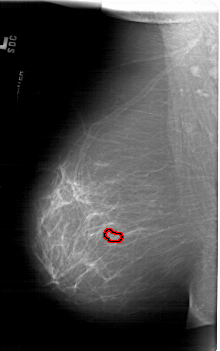

A_1719_1.LEFT_MLO

FILE: A_1719_1.LEFT_MLO.OVERLAY

TOTAL_ABNORMALITIES 1

ABNORMALITY 1

LESION_TYPE MASS SHAPE LOBULATED MARGINS MICROLOBULATED

ASSESSMENT 4

SUBTLETY 3

PATHOLOGY BENIGN

TOTAL_OUTLINES 1

BOUNDARY